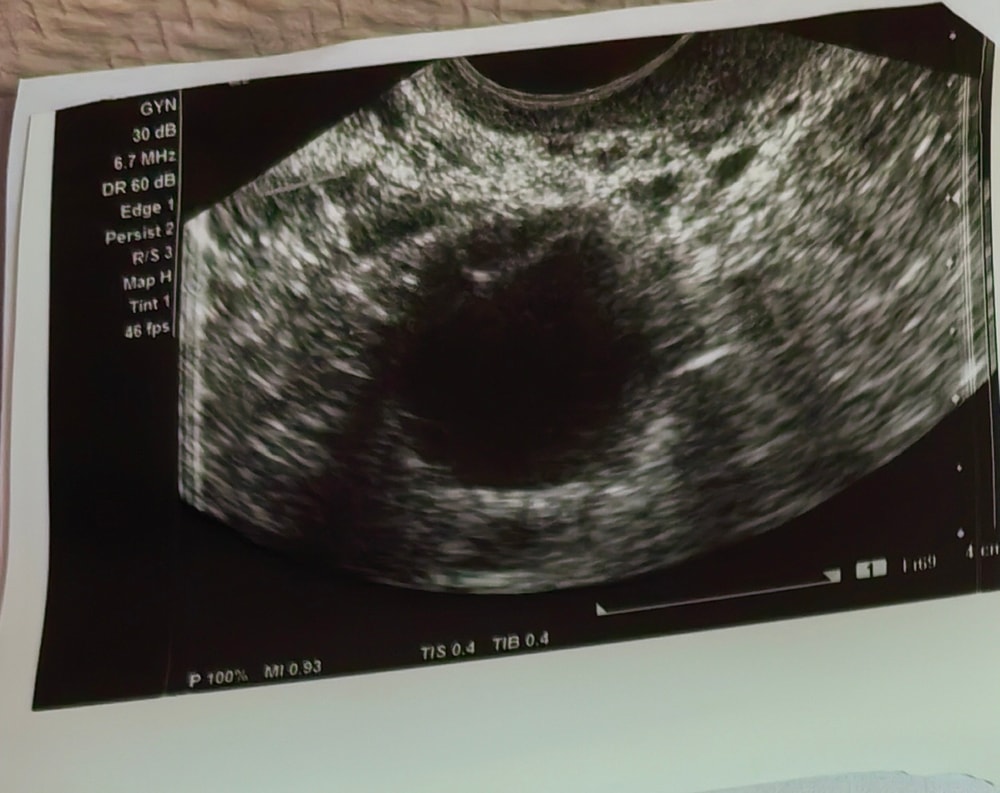

Описание УЗИ: жидкостное образование

Скажите пожалуйста это киста или ж/т по описанию узистка пишет что жидкостное образование с неровными контурами размер 22*16

Киста. У желтого тела другая структура совсем, там не просто жидкость, а разного рода клетки и кровеносные сосуды, которые питают эти клетки. И это все прекрасно видно на узи.

У фолликула жидкостная структура, например, тоже.

Узист бы так и написала - желтое тело или дом фолликул).

При дом фолликуле 19 не может быть желтого тела, овуляции еще не было и выглядит оно иначе.